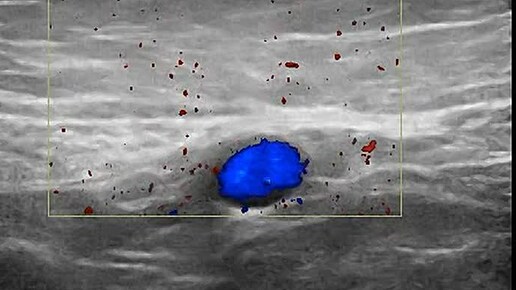

Видео к статье: "СЛУЧАЙ ДИАГНОСТИКИ СОЧЕТАННОЙ ПАТОЛОГИИ "Адрес: https://dzen.ru/a/aQRH94-8ajiog_3_

Ультразвуковые находки от врача УЗД Зорина Я.П.